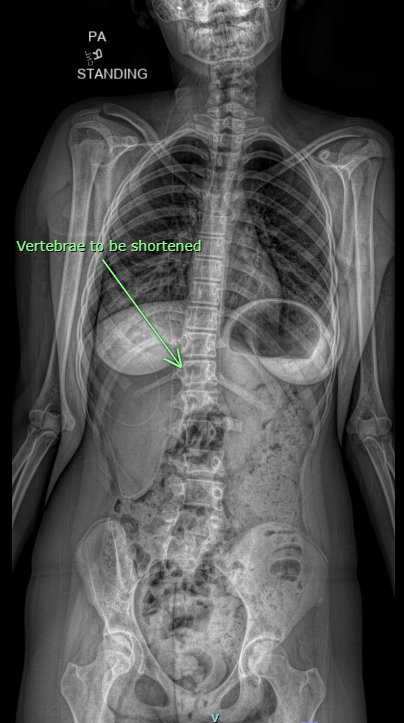

In her latest surgery, Dr. Yengo-Kahn performed a newer procedure that involved taking a vertebra out of her spine to make it shorter. A common alternative technique involves snipping away at the scarring around the spinal cord until it falls back into place. That technique, however, has an elevated risk of neurological problems.

Four patients required partial or complete removal of vertebrae to achieve effective corrections or to improve spinal cord function.

One felt his legs go wobbly and numb when skateboarding. Dr. Aminian and Dr. Yengo-Kahn corrected his condition — congenital scoliosis with thoracic myelopathy (compression of the spinal cord) — by removing the bones in his spine that were pushing against his spinal cord.